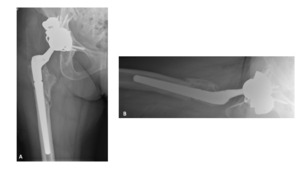

A 63-year-old female presented with recurrent THA instability - verbal consent was obtained for this report. She underwent L2-S1 posterior stabilization with L2-L3 anterior lumbar interbody fusion in May 2002 (Figure 1) and an uncomplicated right THA in April 2007. (Figures 2a-b) Five years following primary THA (July 2011), the patient sustained her first THA dislocation, which was treated with a closed reduction. Between 2011 and 2018, the patient had seven repeat episodes of hip instability – in 2012, one was complicated by a peri-prosthetic femur fracture requiring three revisions and reconstruction with a trochanteric claw plate. She was subsequently diagnosed with a prosthetic joint infection (PJI) which required an antibiotic spacer and subsequent re-implantation three months later. (Figures 3a-b) Following treatment of initial instability and femur fracture, the implants included a size 16 standard taper femoral stem and a 50-mm acetabular shell with 32-mm liner.